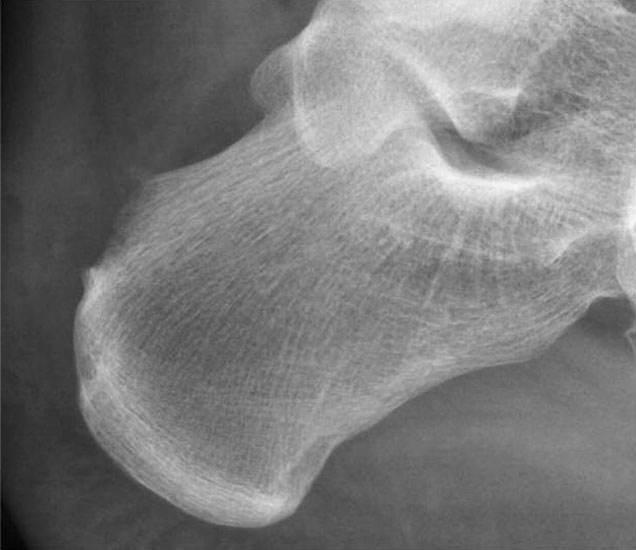

Abbildung 11-12

Prä- und postoperatives Röntgenbild.